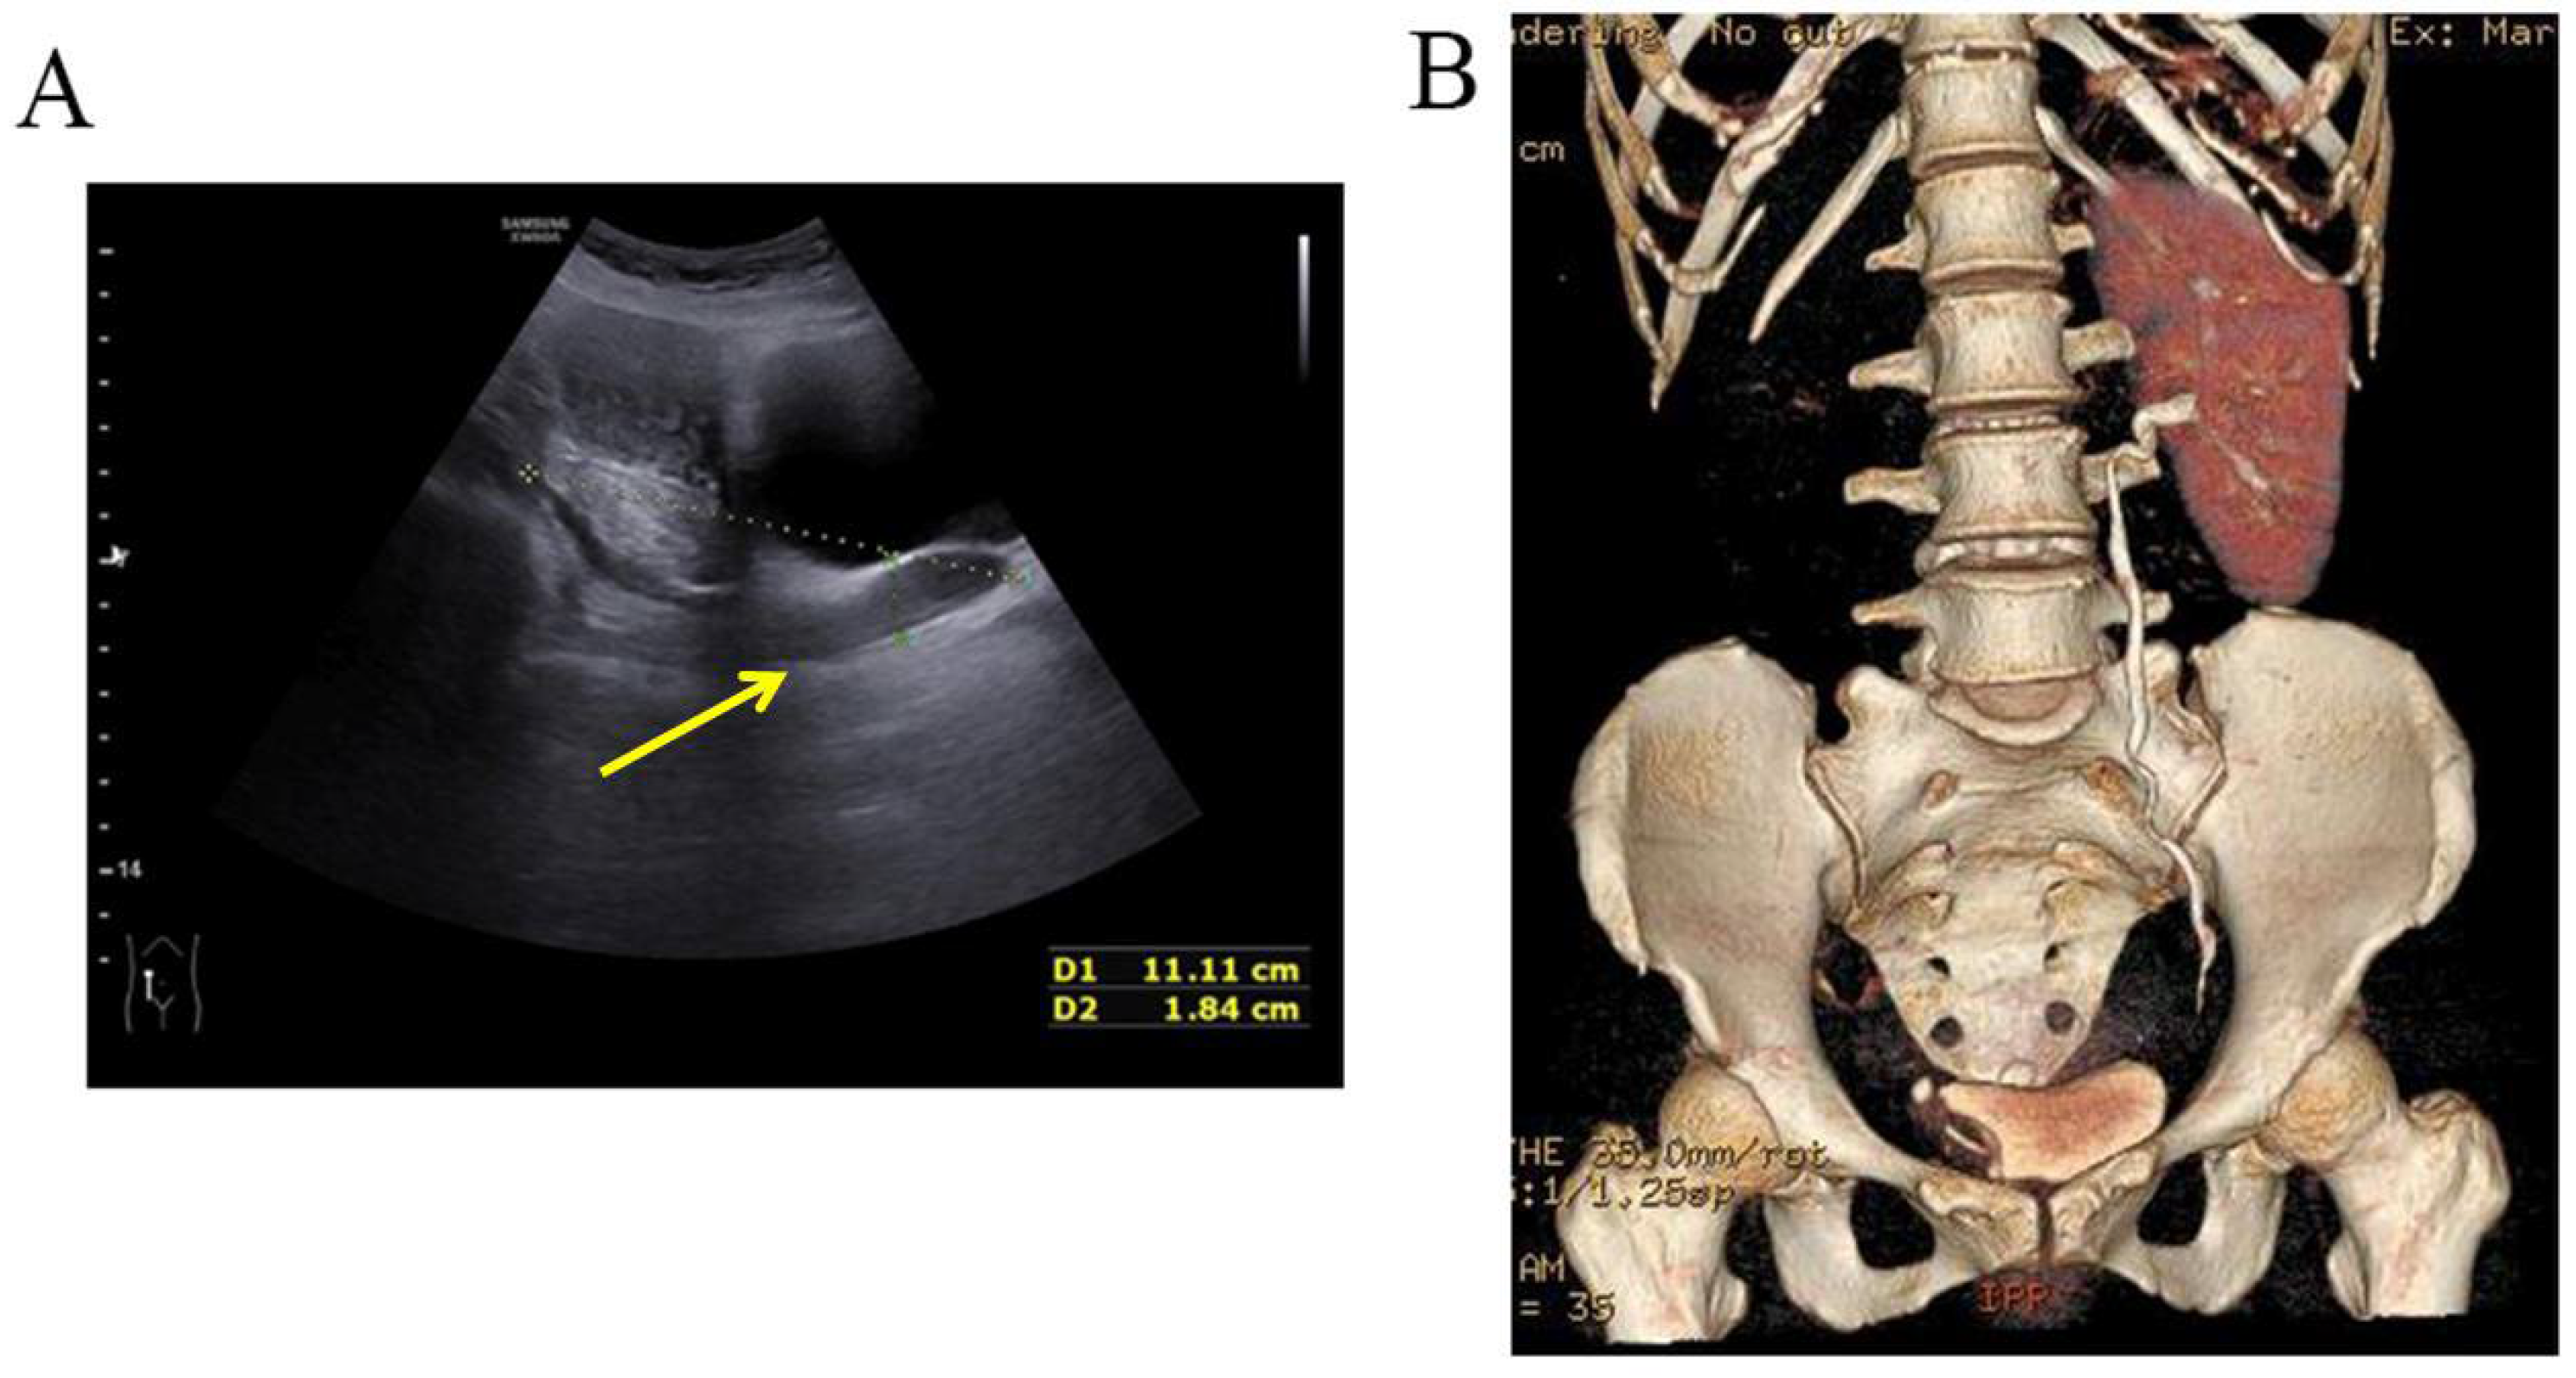

A three-dimensional transvaginal ultrasound revealed adenomyosis and a septate uterus (Figure 1). Two cystic masses with thick internal fluid measuring 3.7 × 4.2 × 2.7 cm (Figure 1A) and 7.5 × 3.1 × 2.1 cm (Figure 1B) were seen on the right side of the uterus, respectively. These cystic masses were considered to be a hydroureter with vaginal fistula. A urinary tract ultrasound revealed the absence of a right kidney, as well as a dilated right ureter measuring 11.1 × 1.8 cm with an ectopic opening into the right vagina (Figure 2A). A computed tomography urography (CTU) revealed the absence of the right kidney (Figure 2B). A pelvic MRI showed a cystic mass considered to be a mesonephric cyst on the right side of the pelvis, bladder, and urethra (Figure 3A). A complete septate uterus with multiple fibroids was also found (Figure 3B). The creatinine concentration of the fluid inside the pelvic cyst was measured to be 157 nmol/L via transvaginal aspiration (Figure 4).

Figure 2.

Malformations of the urinary tract. (A) Urinary tract ultrasound demonstrated the absence of right kidney, right ureteral dilatation, and right ectopic ureter. (B) CTU demonstrated the absence of right kidney.